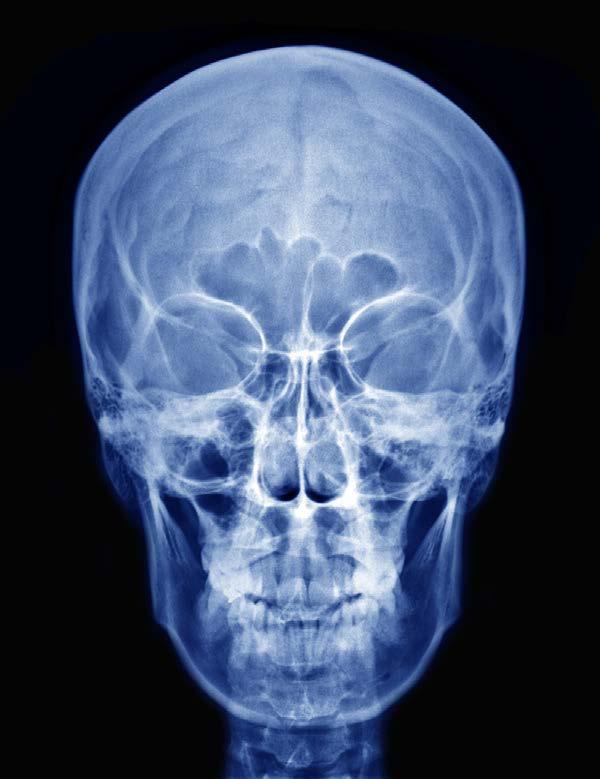

AudioLearn's Medical School Crash Courses presents Radiology